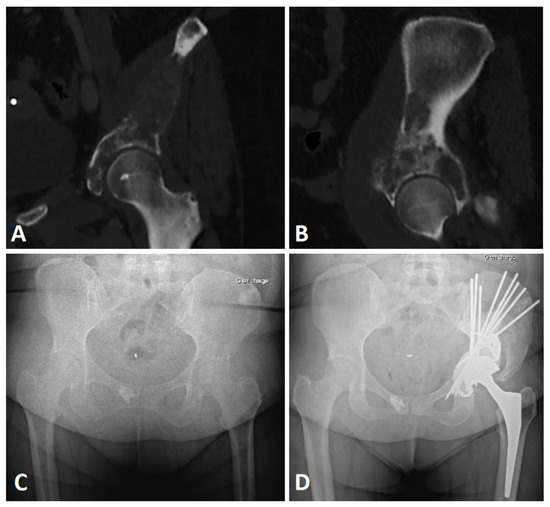

2.2. Extensive Acetabular Bone Loss Management

2.2.1. Treatment Strategy

2.2.2. Surgical Procedure

| Harrington Grade | Grade 2 | 8 (32.3%) | |

| Grade 3 | 14 (66.7%) | ||

| Enneking Zones | Zone 1 | 10 (47.6%) | |

| Zone 2 | 21 (100%) | ||

| Zone 3 | 3 (14.3%) | ||